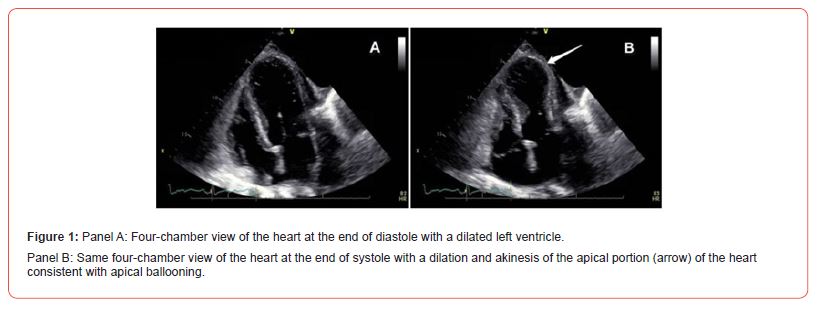

PCI was completed successfully using two DCBs for the mid RCA and mid LAD lesions. Post-procedure, she required moderate inotropic support to maintain systolic BP >100 mmHg. Chest X-Ray consistent with acute heart failure, mild-moderate in severity. Echocardiography revealed apical ballooning and EF <30% (Figure 1). Troponin levels were elevated at four times the upper limit of normal, with normal CK-MB levels. NT-pro-BNP was markedly elevated the following day. She developed acute kidney injury with creatinine peaking at 4 mg/dL (GFR <30 mL/min/1.73m²). The diagnosis of propofol-induced Takotsubo cardiomyopathy was established.